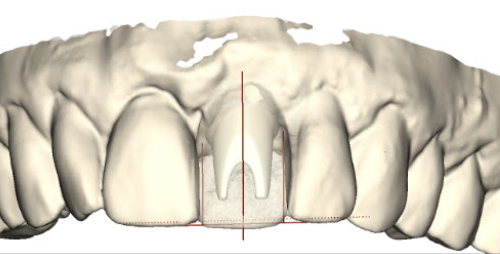

(29.) Single anterior custom abutment workflow.

Figure 29

(30.) Single anterior custom abutment workflow.

Figure 30

(31.) Single anterior custom abutment workflow.

Figure 31

(32.) Single anterior custom abutment workflow.

Figure 32

(33.) Single anterior custom abutment workflow.

Figure 33

(34.) Single anterior custom abutment workflow.

Figure 34

(35.) Single anterior custom abutment workflow.

Figure 35